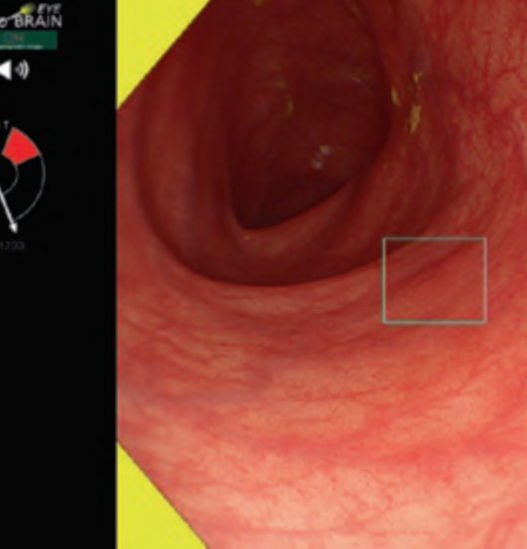

The flat pattern is a unique mucosal surface in BE showing an invisible/absent mucosal pattern, corresponding not to dysplastic but to non-dysplastic histology. The flat pattern was originally defined as invisible mucosal pattern (i.e., absence of pits and villi) with normal-appearing, long branching vessels. The flat pattern mimics an absent micro-surface (mucosal) pattern, which is significantly suggestive of early gastric cancer. As it was difficult for clinicians working in areas with a high incidence of gastric cancer to rate the flat pattern as non-dysplastic, recent studies proposed modified criteria for the “flat pattern.” This was to enhance the diagnostic accuracy for non-dysplastic lesions. This study used the modified criteria; according to these criteria, an invisible mucosal pattern without a distinct demarcation line and visible vascular patterns of long branching vessels or greenish thick vessels (GTV) was rated as “regular.” Thus, a flat pattern was rated as “regular” and the predicted histology as “non-dysplastic.” . Figure 3 shows representative NBI-M images of the flat pattern according to the modified criteria.

By using the diagnostic flowchart of the JES-BE classification (. Fig. 1), first, the mucosal pattern was classified as “visible” or “invisible” and rated as “regular” or “irregular” based on the diagnostic criteria for irregularity, as reported previously. The “invisible” mucosal pattern cannot be rated. Second, the vascular pattern was classified as “visible” or “invisible.” The “visible” vascular pattern included normal- appearing, long branching vessels and GTV previously reported and after- mentioned. General diagnosis was rated as “regular” or “irregular” based on mucosal plus vascular patterns. Finally, histology (“non-dysplastic” vs. “dysplastic”) was predicted according to the general diagnosis. “Dysplastic” corresponds to SBERN, including low-grade dysplasia (LGD), high-grade dysplasia (HGD), and superficial adenocarcinoma. Representative NBI-M images are shown in Fig. 4.